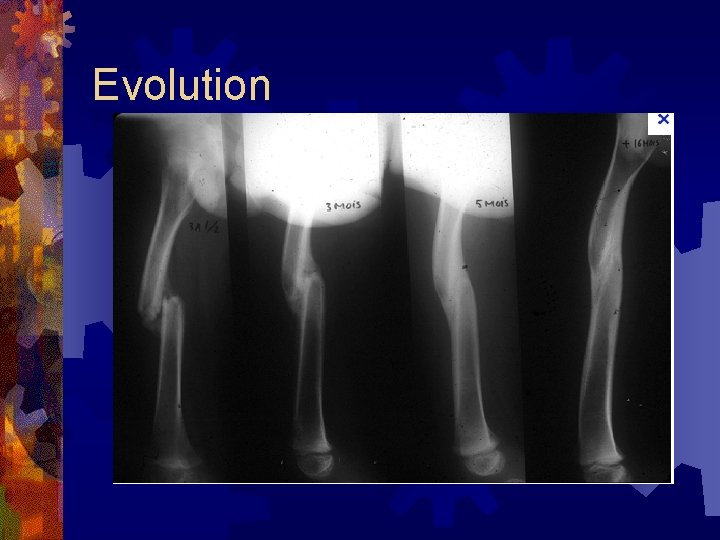

Evolution